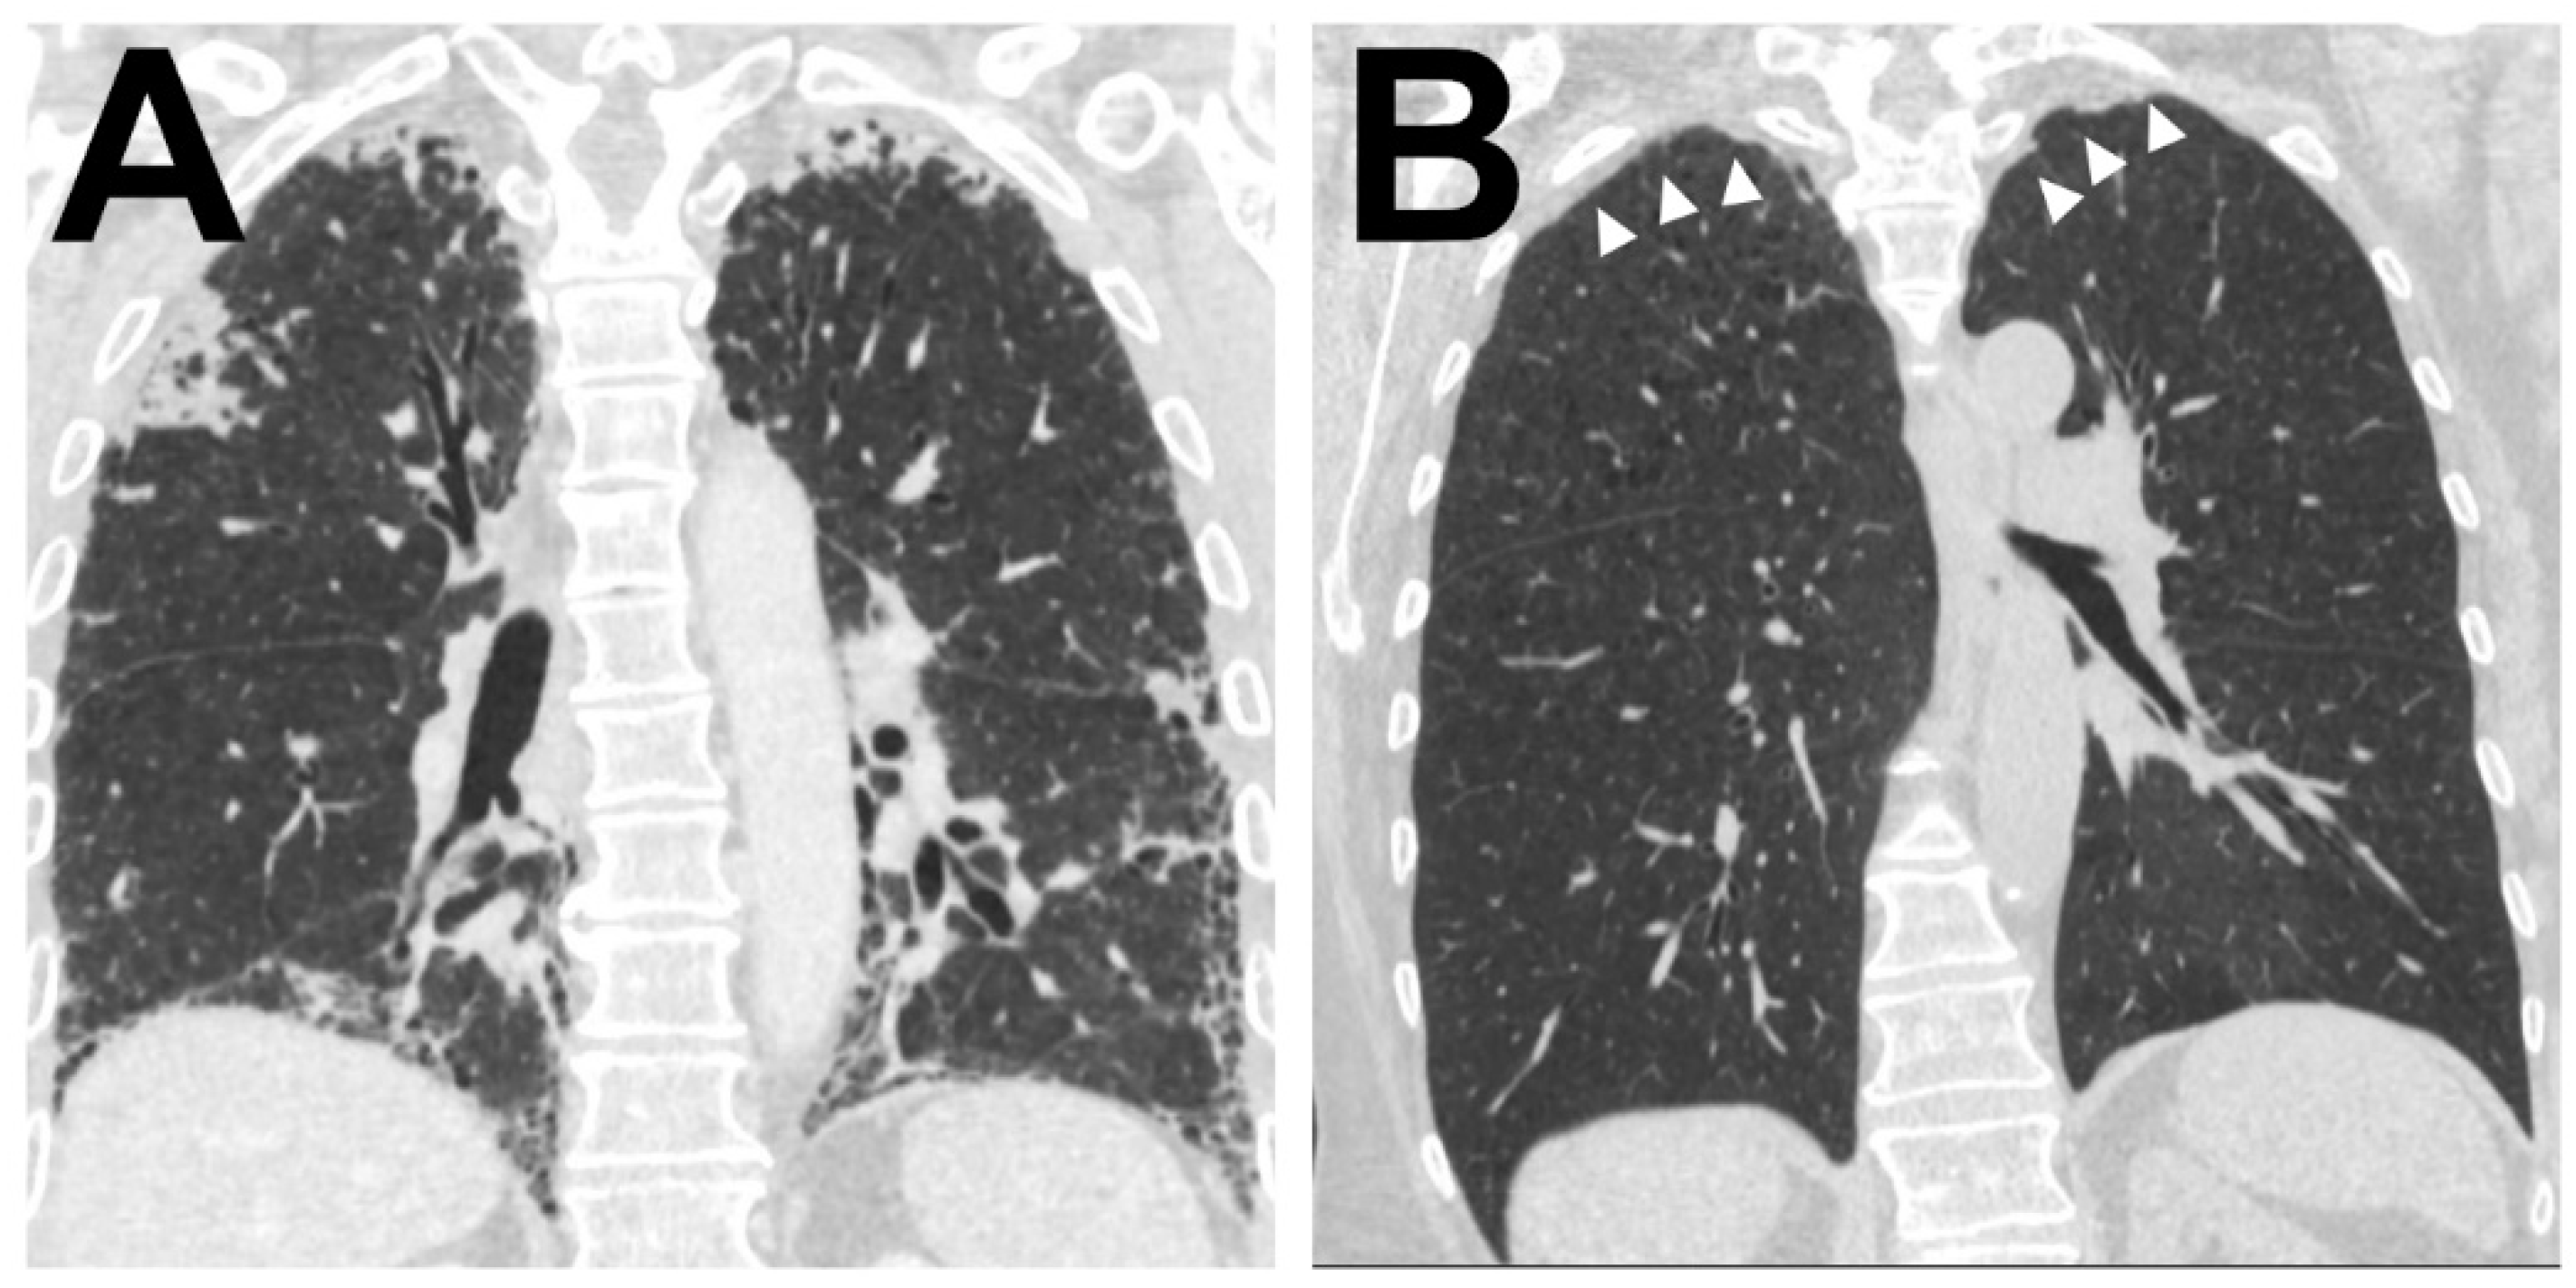

Within areas of typical AFE, the pattern of intra-alveolar fibrosis/fibrotic obliteration was classified as coarse fibrillary if broad hyalinised bundles of collagenous fibres (usually ~2 µm in diameter) were present and as fine fibrillary if delicate, mostly curled fibres were demonstrable. The presence of anthracophages and lymphoid aggregates was noted as well as an increase in cellularity with diffuse infiltration of lymphocytes or the presence of an increased number of mesenchymal cells such as (myo) fibroblasts in the obliterated alveolar lumen (see Figure 1).

In the majority of cases (67%) both coarse and fine fibrillary fibrosis could be detected, in the other cases either only fine fibrillary or only coarse fibrillary fibrosis (20% and 13% respectively) were detectable. Features found regularly in areas of AFE were aggregates of lymphatic cells (73%), often at the leading edge of the remodelling process (see Table 4). These appear well circumscribed, organized in an organoid manner, sometimes contain specialized vessels with the appearance of highly endothelialised venules (HEV) and can be distinguished from a diffuse infiltration of the AFE lesion by lymphatic cells which can be observed in approximately 30−40% of cases. Macrophages containing phagocytosed anthracotic pigment can be detected in 53% of total cases and appear less frequently in patients of the HSCT group (14%). Typical fibroblastic foci (FF) could be detected in 11% of cases. Overall, the areas of AFE showed similar morphological characteristics in all investigated groups. PAC showed overall less cellular mesenchymal (0%) and lymphatic (7%) infiltration when compared to the PPFE and PPFE-like cases (45% and 45% respectively).

We observed and catalogued several morphological patterns in direct spatial association with regions of typical AFE. Besides structurally intact lung parenchyma, various forms of FER with either fibro-elastic expansion of alveolar septa, incomplete alveolar fibrosis, or irregularly distributed collagenous and elastic fibers could be observed (See Figure 2 and Table 3 for a comprehensive list of catalogued features).

In the majority of cases (93%) fibroelastic expansion of alveolar septa could be observed at the border of typical AFE besides a direct and abrupt transition to structurally intact alveolar parenchyma (91%). In 84% of cases, areas of incomplete fibroelastosis could be detected. Frequently, pleural fibrosis could be observed adjacent to typical AFE (79%).

Figure 2. Typical histological patterns in special association with alveolar fibroelastosis (AFE). A set of typical features regularly found in spatial association with AFE: (A) Pronounced fibrosis of the visceral pleura. (B) Emphysema with an irreversible loss of alveolar septa. (C) Elastosis of the alveolar wall with incomplete alveolar fibrosis of the alveolar lumen with residual airspaces lined by cuboidal epithelium (*). (D) Fibroelastic interstitial expansion of the alveolar septa adjacent to the AFE lesion. (E) Aggregates of intraalveolar macrophages. (F) Cholesterol granulomas with multinucleated giant cells with clefts of cholesterol crystals. (G) Bronchiolitis obliterans with fibrous obliteration of small airways and (H) sclerosis of pulmonary arteries with hypertrophy of the media and intimal hyperplasia. Images are elastic van Gieson stains. Scale bars are 100 µm each.